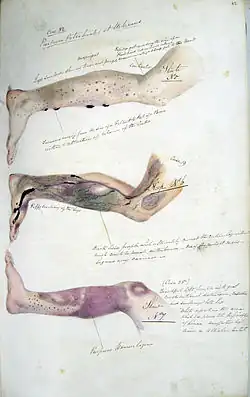

.jpg) A neglected child presenting a "scorbutic tongue" due to vitamin C deficiency

A neglected child presenting a "scorbutic tongue" due to vitamin C deficiency -

A child patient with scurvy in flexion posture

A child patient with scurvy in flexion posture -

Photo of the chest cage with scorbutic rosaries

Photo of the chest cage with scorbutic rosaries